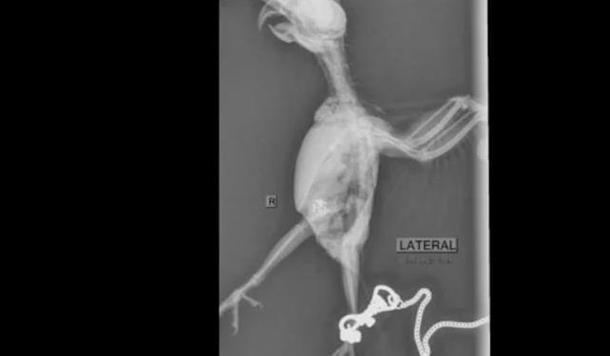

После этого птица ослабла и больше не хотела есть. Попугая отвезли в ветклинику и сделали рентген, который показал, что в желудке птицы есть инородные тела.

Фрости вскрыли желудок и вытащили 21 камень весом по 0,2 карата.